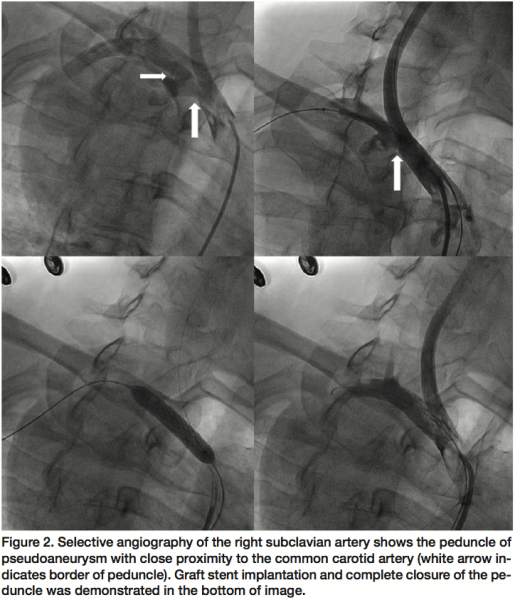

The endovascular procedure was performed via access through the right femoral artery. The pseudoaneurysm was found (angiographically) to communicate with the main subclavian artery via a relatively large 10 mm neck that was in close proximity to the origin of the right common carotid artery. More detailed visualization of the carotid artery and innominate artery bifurcation was afforded by placement of a guidewire into the carotid artery from the left femoral artery. Endovascular exclusion of the pseudoaneurysm was achieved with deployment of a 12 x 28 mm balloon-expandable peripheral stent-graft (Jostent, Abbott Vascular) within the lumen of the right subclavian artery in the segment between the innominate artery bifurcation and the origin of the right vertebral artery. Both the carotid artery and vertebral artery orifices were spared. Completion angiography showed complete closure and exclusion of the pseudoaneurysm (Figure 2). The patient was discharged the next day without complications and a control MRI examination was scheduled 3 months later to assess the final anatomic result and determine whether additional open surgical treatment was necessary.